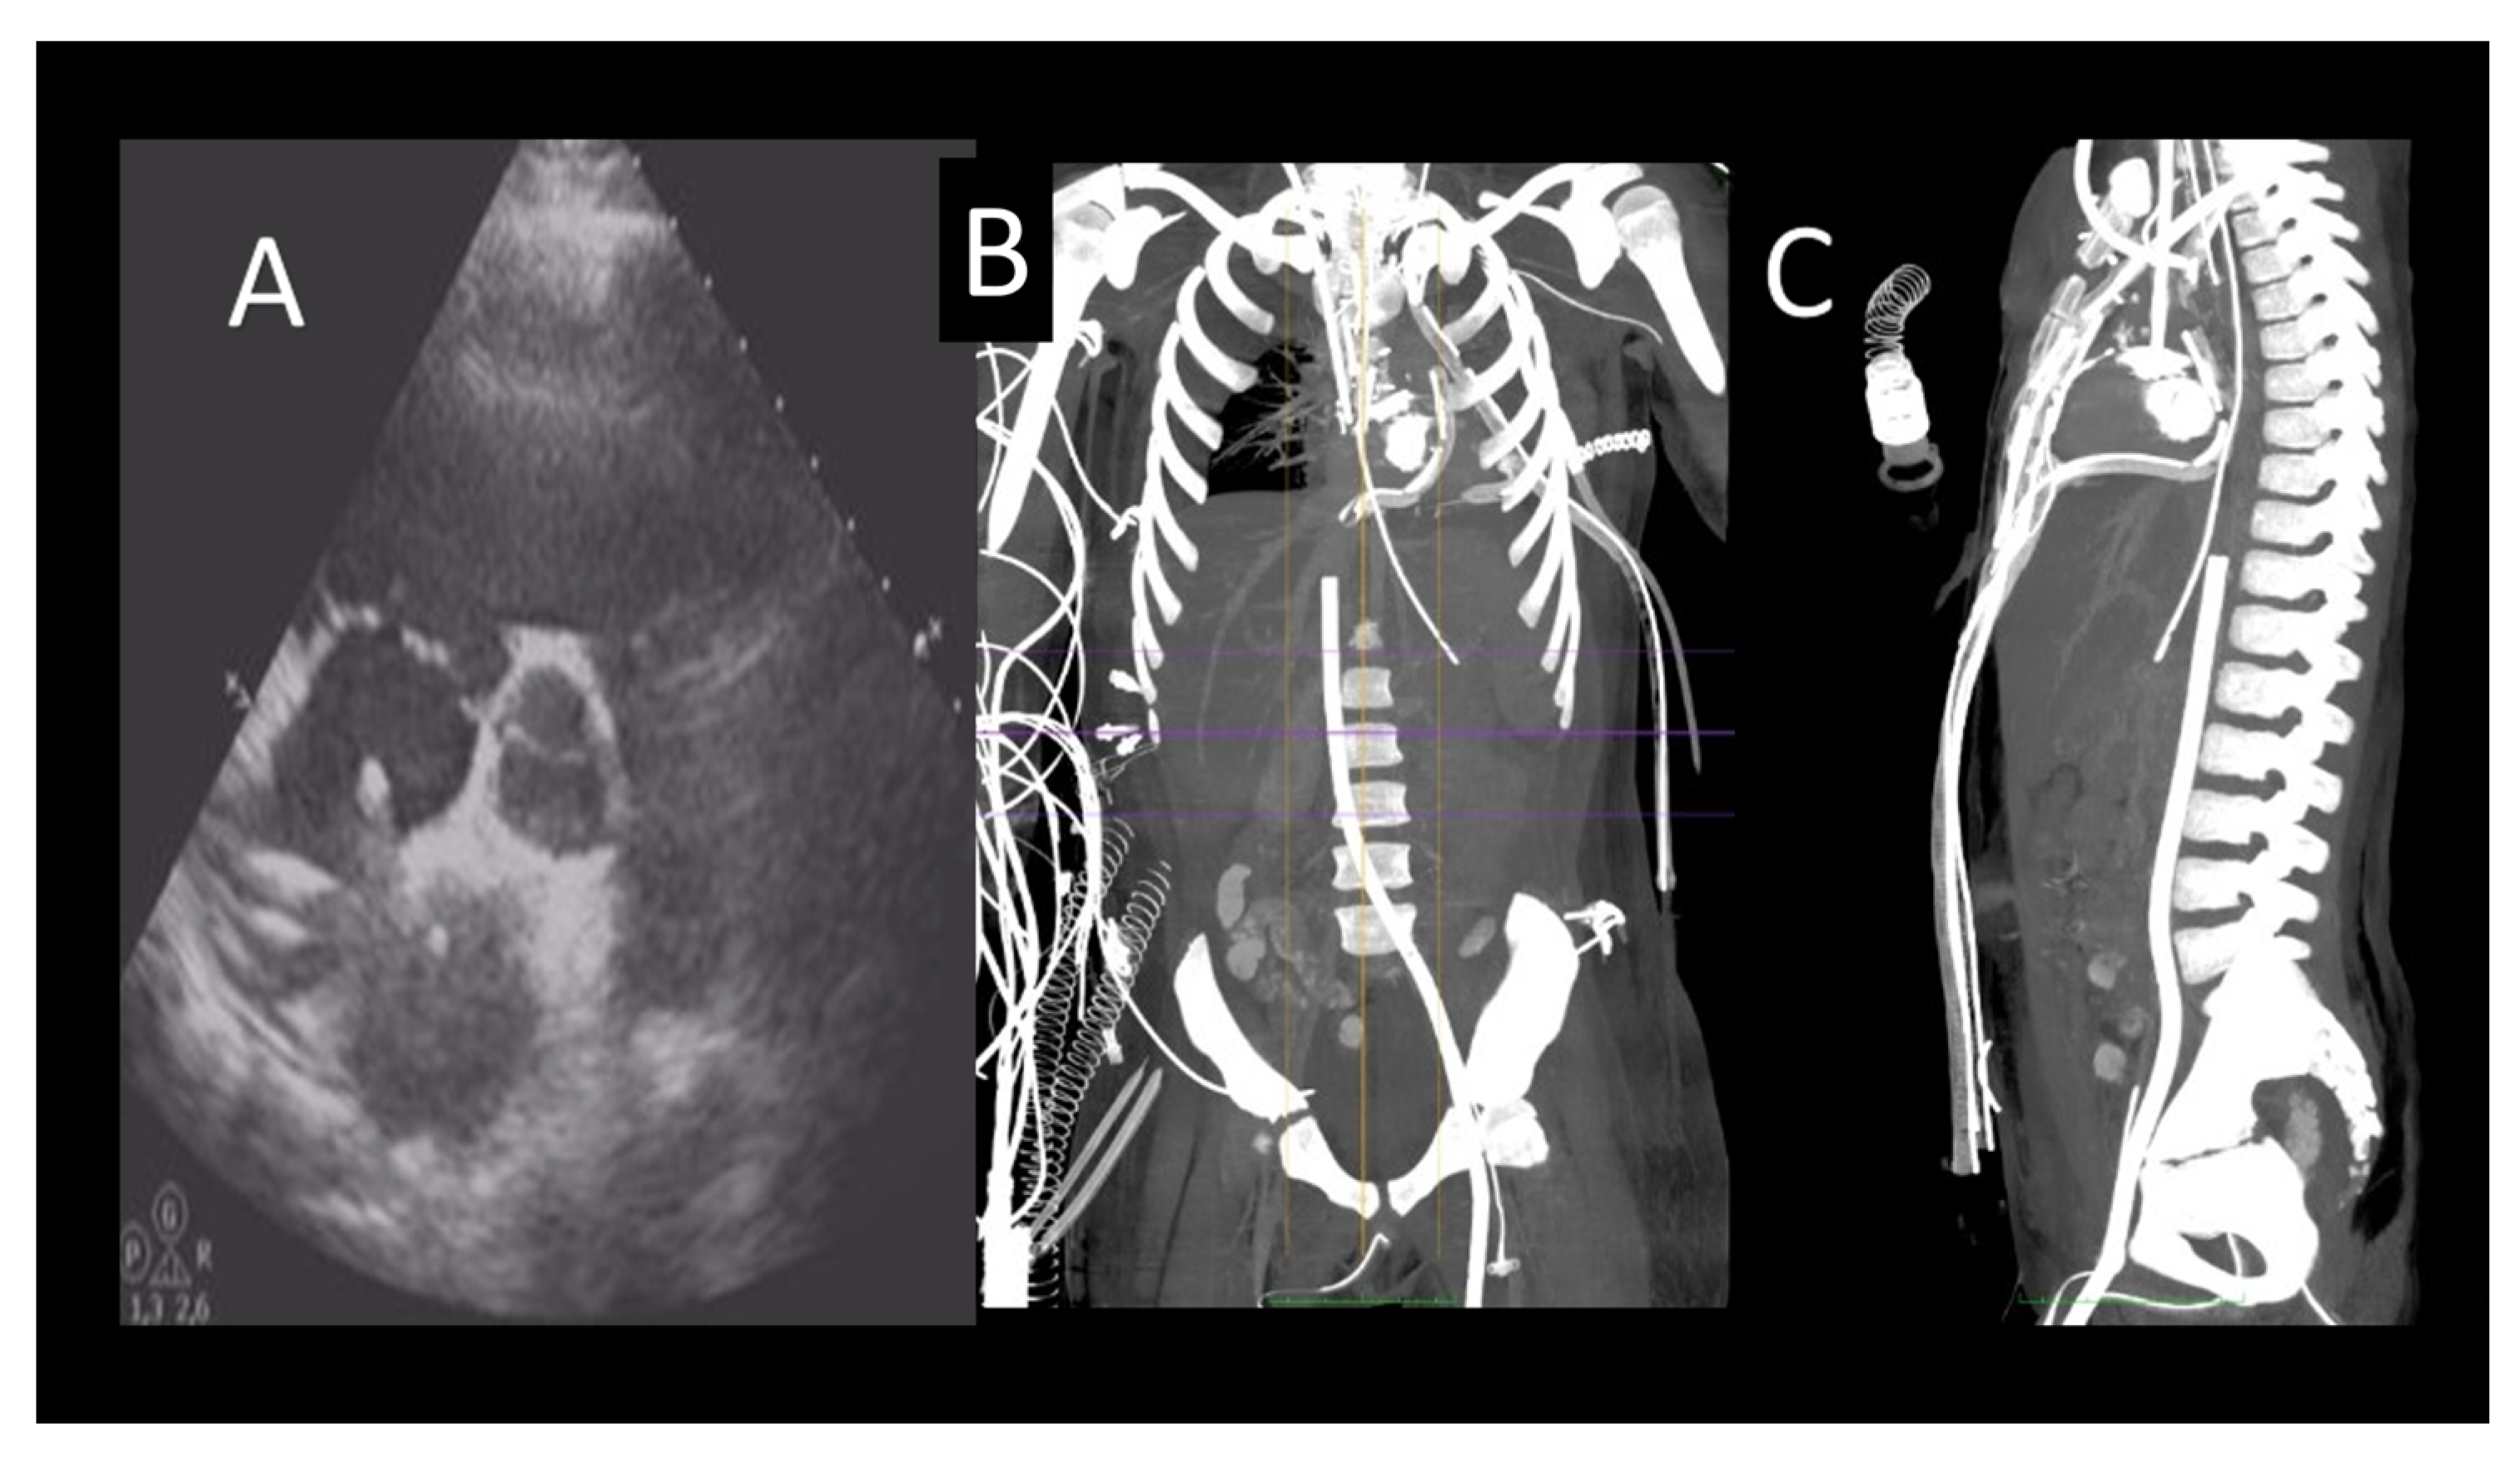

2.2. Short-Term Mechanical Support

2.2.1. The Intra-Aortic Balloon Pump

- Anand, S.; Barry, T.; Arsanjani, R.; LeMond, L. Echocardiography in Cardiac Assist Devices. Rev. Cardiovasc. Med. 2022, 23, 253. [Google Scholar] [CrossRef]

- Crowley, J.; Cronin, B.; Essandoh, M.; D’Alessandro, D.; Shelton, K.; Dalia, A.A. Transesophageal Echocardiography for Impella Placement and Management. J. Cardiothorac. Vasc. Anesthesia 2019, 33, 2663–2668. [Google Scholar] [CrossRef] [PubMed]

- Pieri, M.; Pappalardo, F. Bedside insertion of impella percutaneous ventricular assist device in patients with cardiogenic shock. Int. J. Cardiol. 2020, 316, 26–30. [Google Scholar] [CrossRef]

- Yastrebov, K.; Brunel, L.; Paterson, H.S.; Williams, Z.A.; Wise, I.K.; Burrows, C.S.; Bannon, P.G. Implantation of Impella CP left ventricular assist device under the guidance of three-dimensional intracardiac echocardiography. Sci. Rep. 2020, 10, 17485, Erratum in Sci. Rep. 2021, 11, 5091. [Google Scholar] [CrossRef]

- Nakao, Y.; Aono, J.; Namiguchi, K.; Nishimura, T.; Izutani, H.; Higashi, H.; Inaba, S.; Nishimura, K.; Inoue, K.; Ikeda, S.; et al. Usefulness of contrast computed tomography for diagnosing left ventricular thrombus before impella insertion. J. Cardiol. Cases 2020, 22, 291–293. [Google Scholar] [CrossRef] [PubMed]

- Lee, S.; Chaturvedi, A. Imaging adults on extracorporeal membrane oxygenation (ECMO). Insights Imaging 2014, 5, 731–742. [Google Scholar] [CrossRef] [PubMed]